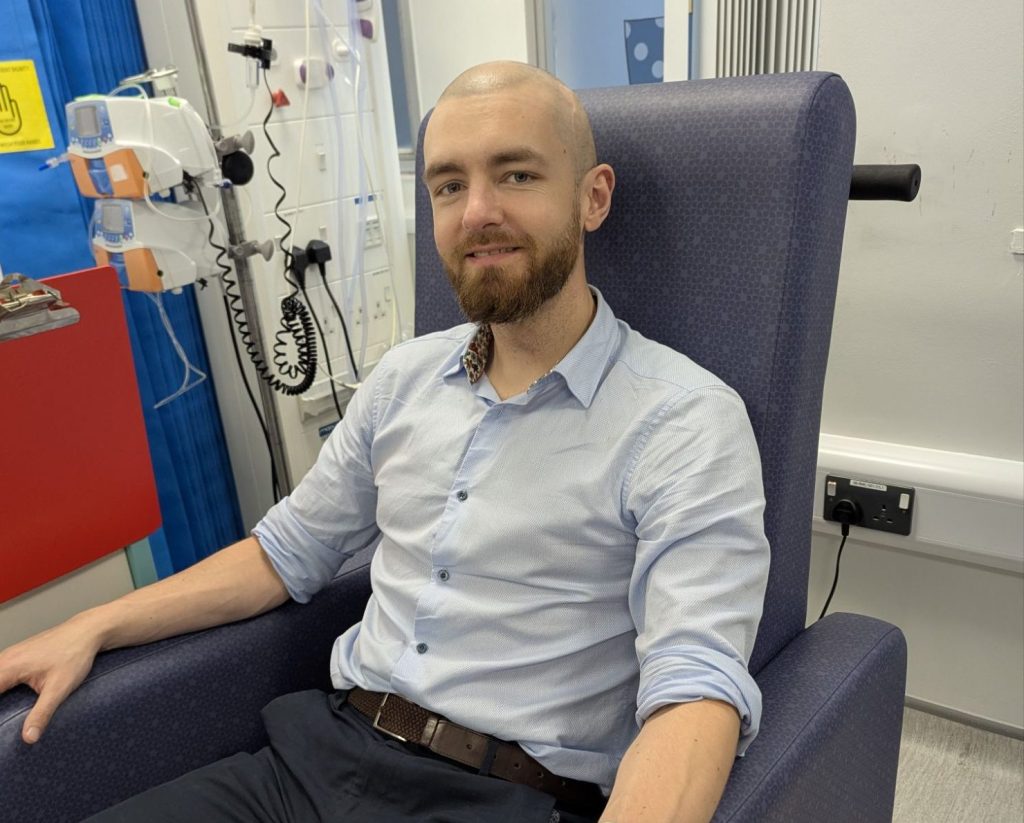

Returning to work felt like pulling the ripcord mid-freefall, a sudden jolt, a rush of movement, and then, finally, a slow drift back toward something that looked and felt like stability. Serenity and silence for my mind. At least for a little while.

About my Story

I am committed to bringing you my true, raw and unfiltered experiences living with a brain tumour. Expect a humorous take on a gritty and often difficult subject. Through the lens of positivity, I examine the daily struggles and challenges of those of us living with brain tumours.

I aim to advocate, educate and shed light on an often misunderstood subject.